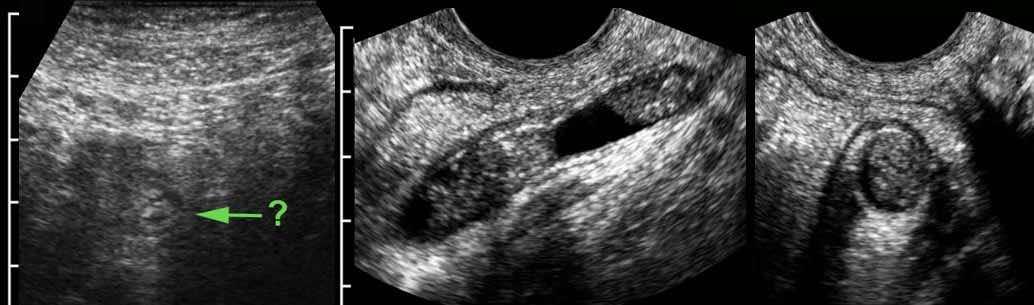

Ở người phụ nữ mang thai 11 tuần này, siêu âm xác nhận thai trong tử cung còn nguyên vẹn đồng thời phát hiện viêm ruột thừa cấp.

Lưu ý sự khác biệt về thang đo cm.

Phẫu thuật nội soi cắt bỏ ruột thừa viêm đã được thực hiện thành công.

Ở người phụ nữ mang thai và béo phì này, một ruột thừa có thể đang viêm (mũi tên kèm dấu hỏi) được quan sát thấy khi ấn mạnh sâu xuống vùng tiểu khung.

Siêu âm qua đường âm đạo tiếp theo cho thấy một ruột thừa đang viêm chứa đầy mủ, nằm trong vòng 1 cm so với đầu dò âm đạo.